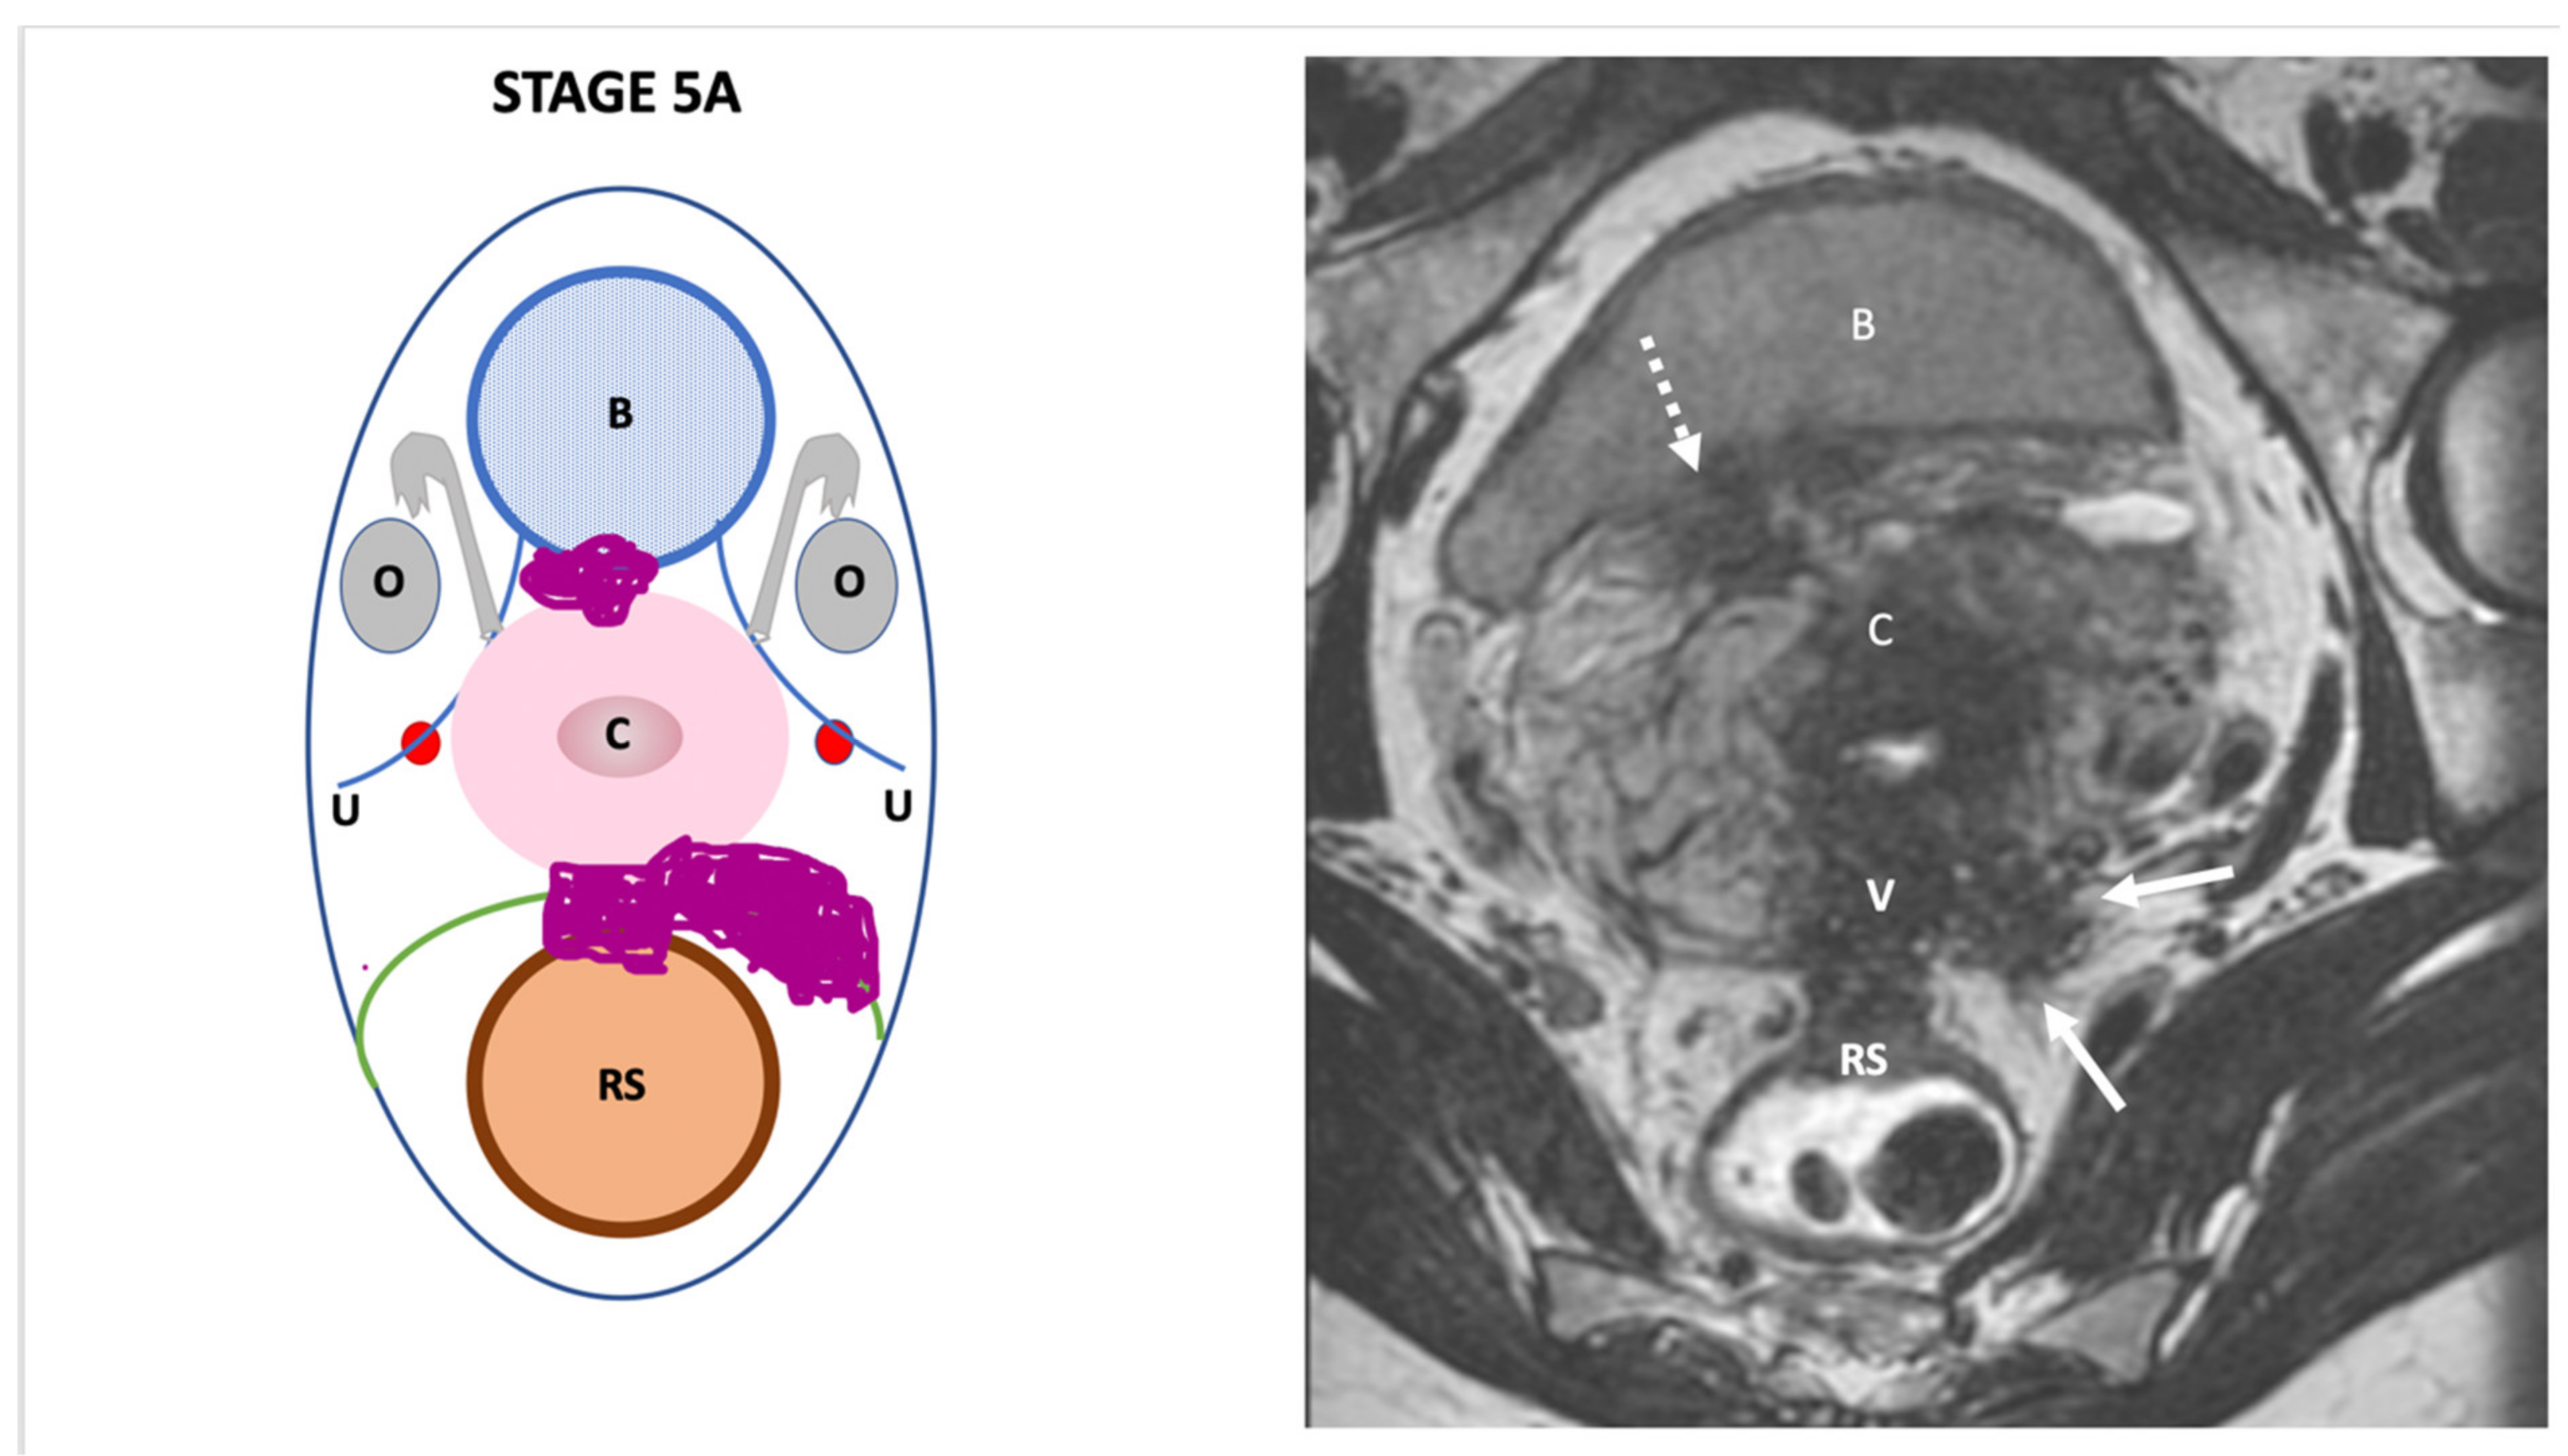

| Endo-Stage MRI 0 | Superficial endometriosis |

| Low |

| Endometriosis is strictly confined to the ovaries |

| ||

| Endo-Stage MRI I | Endometriosis is strictly confined to the retrocervical area |

| |

| Endo-Stage MRI II | Endometriosis invades beyond the retrocervical area, but not to the pelvic side-wall |

| Endo-Stage MRI III | Endometriosis extends to the pelvic side-wall and/or causes hydronephrosis or non-functioning kidney |

| Intermediate |

| Endo-Stage MRI IV | Endometriosis has involved the bladder or rectosigmoid colon |

| Endo-Stage MRI V | Multiple deep endometrioticlocations |

| High |